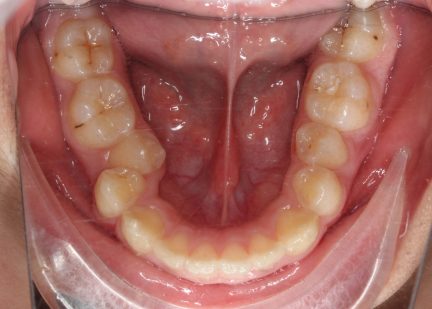

Classe II div 1, surplomb accru, rétrognathie mandibulaire, articulation profonde, arcades étroites, arcades asymétriques, déviation de la ligne médiane mandibulaire, décalage de la ligne médiane, chevauchement

- Courbe de Spee nivelée

- Arcades alignées et coordonnées

- Forme de l'arcade améliorée

État initial

État final